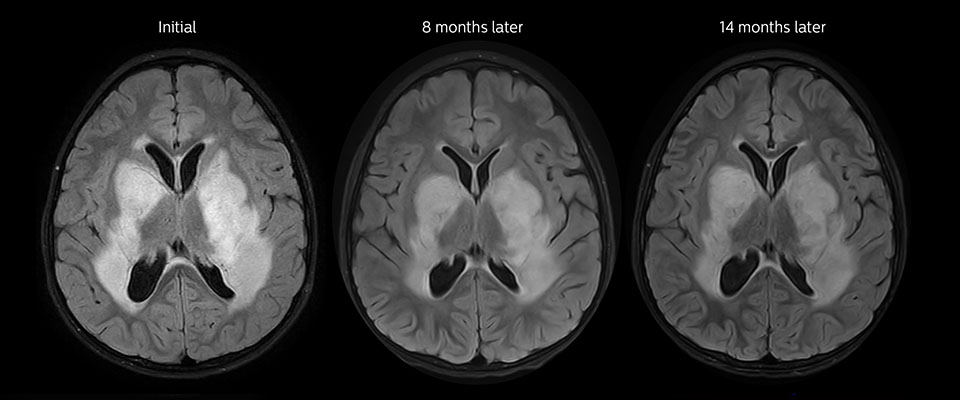

Große metastatische Hirnläsion

Diese 10-jährige Patientin unterzog sich vor 7 Jahren der Resektion eines Ewing-Sarkoms, doch jetzt wurde eine große metastatische Läsion im Gehirn entdeckt. Diese Läsion zeigt deutlich ein erhöhtes APT-Signal.

MRT mit APT nach der Resektion

Unmittelbar nach der Resektion wurde erneut eine MRT durchgeführt. Die T2-gewichteten und kontrastverstärkten T1-gewichteten Bilder lassen keine eindeutige Unterscheidung von Residualtumorgewebe und postoperativen Gewebeveränderungen zu. Auf dem APT-Bild ist noch ein hohes Signal zu sehen, das auf Residualtumorgewebe hindeuten würde.

Nachuntersuchung im Laufe der Zeit

In späteren Nachuntersuchungsscans weisen die kontrastverstärkten T1-gewichteten Bilder auf rezidivierendes Tumorwachstum hin. Daher wäre es interessant, den prädiktiven Wert von APT in einer großen Patientengruppe zu untersuchen.